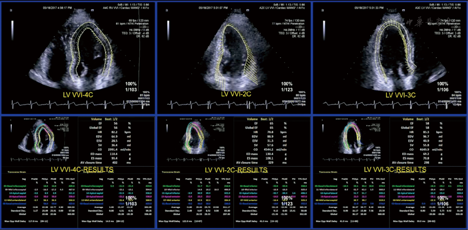

速度向量分析是评估局部心功能的新技术,它不依赖多普勒原理,基于二维灰阶成像的原理,利用超声像素的空间相干、斑点追踪等技术,采集原始的二维像素的振幅及相位信息,计算并以矢量方式显示局部心肌组织真实的活动方向、速度、距离、时相等,对心肌组织在多个平面运动的结构力学进行量化分析。分别在A4C、A2C和A3C勾画心内膜和心外膜边界,即可自动获取3个切面的速度向量图,分析结果中包含每个心肌节段的长轴应变、应变率、位移以及局部EF等内容,它是斑点追踪成像不同的显示模式。见图6。

注:GLPS整体长轴峰值应变;LAX心尖长轴;A4C心尖四腔切面;A2C心尖两腔切面;Avg平均;AVC_AUTO自动获取主动脉瓣关闭时间;HR心率;FR帧频;PSD达峰时间离散指数